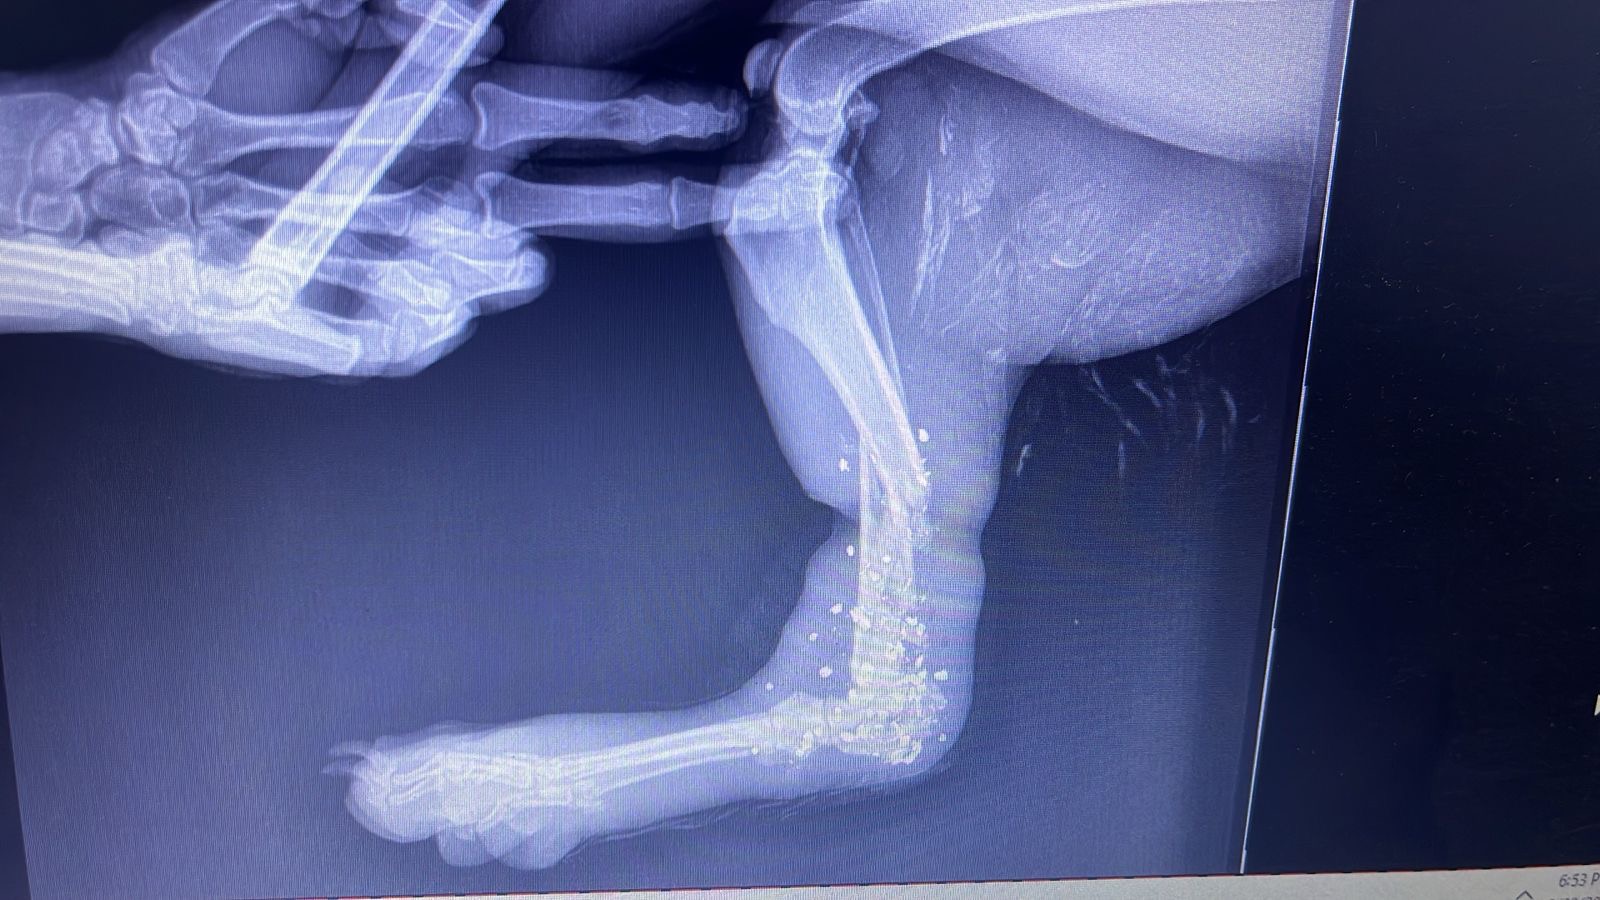

Hello friends and family! This fundraiser is being started for our dog, Pelusa, who was shot in her foot last night. The vet said that the only solution is to amputate her leg since she still has bullet fragments in her leg. Anything is appreciated♥️